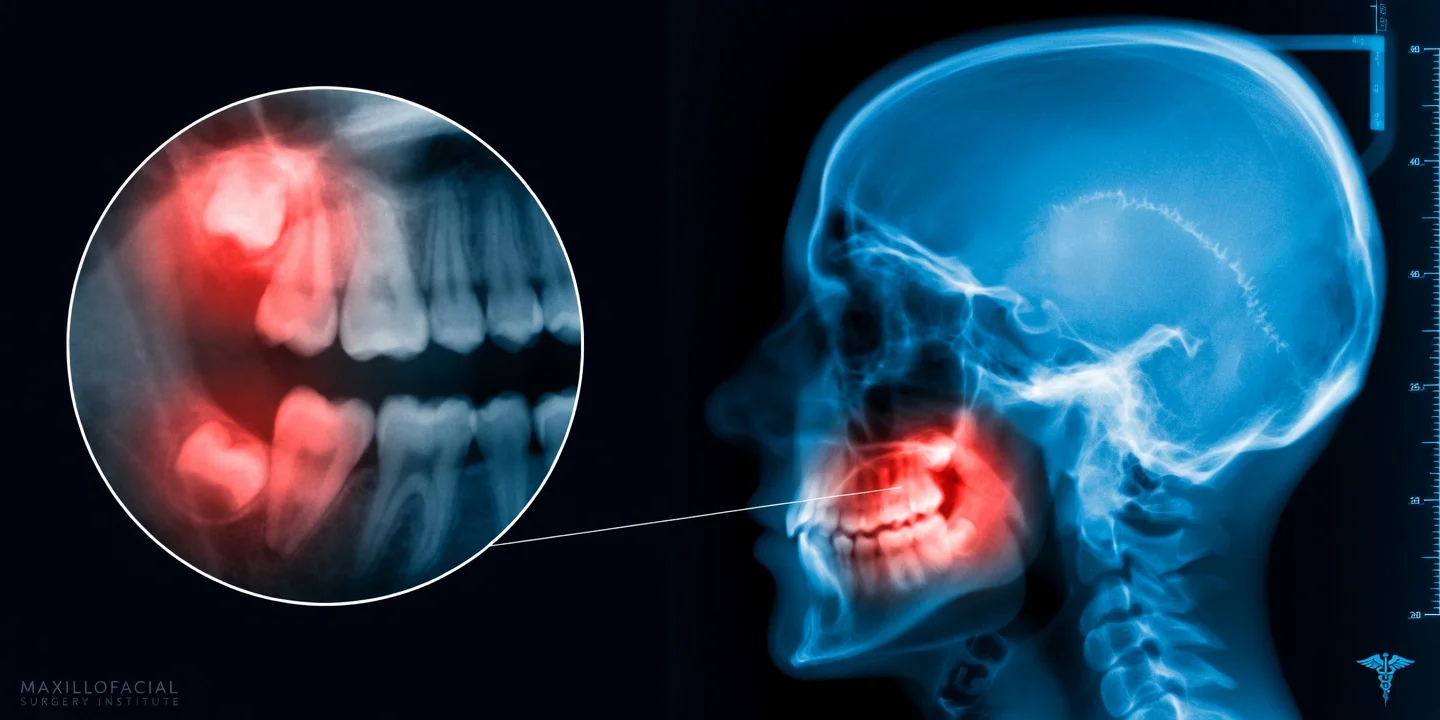

Dentes inclusos são dentes que não nasceram por completo ou ficaram presos no osso e na gengiva. Os sisos são os exemplos mais comuns, mas outros dentes também podem permanecer impactados.

Quando não há espaço adequado, o dente pode empurrar estruturas vizinhas, inflamar a gengiva ao redor, acumular resíduos e dificultar a limpeza. Em alguns casos, a pessoa não sente nada no início, e o problema aparece nos exames de rotina.